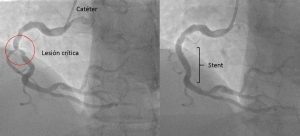

CASO CLINICO DE CATETERISMO CARDIACO + ANGIOPLASTÍA